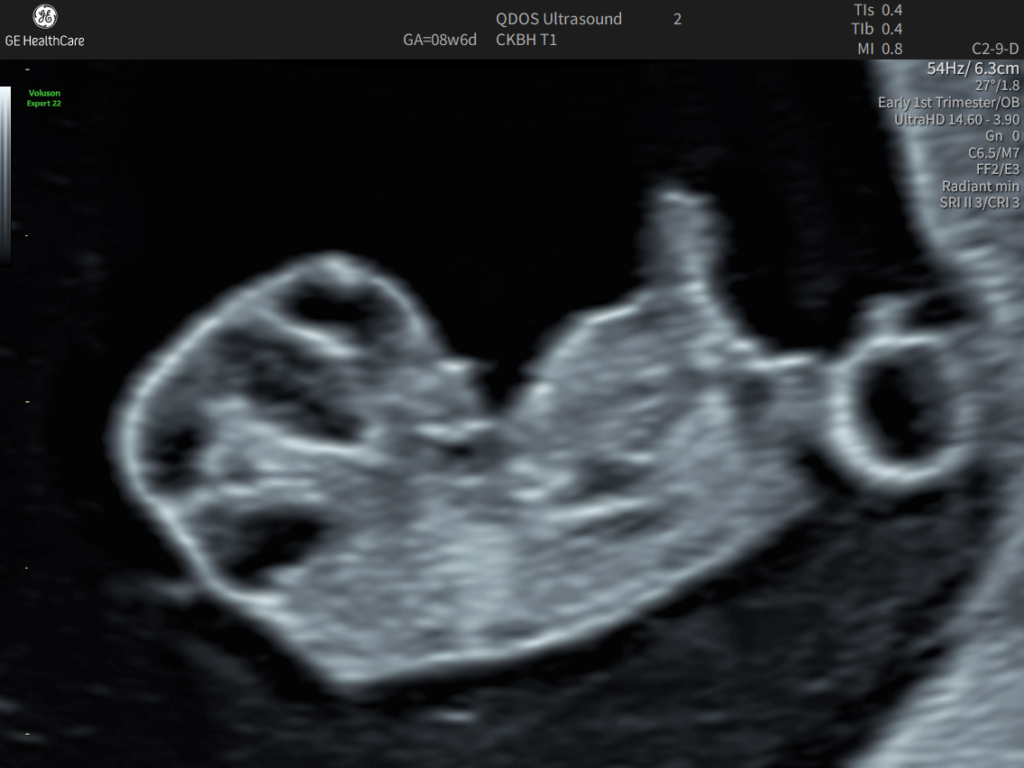

What An Early Pregnancy Ultrasound May Be Able To Detect

• Determine how far along you are and provide an estimated due date.

• Confirm that your pregnancy is progressing as expected and that the baby is in the right place.

• Identify if you are expecting twins or multiples.